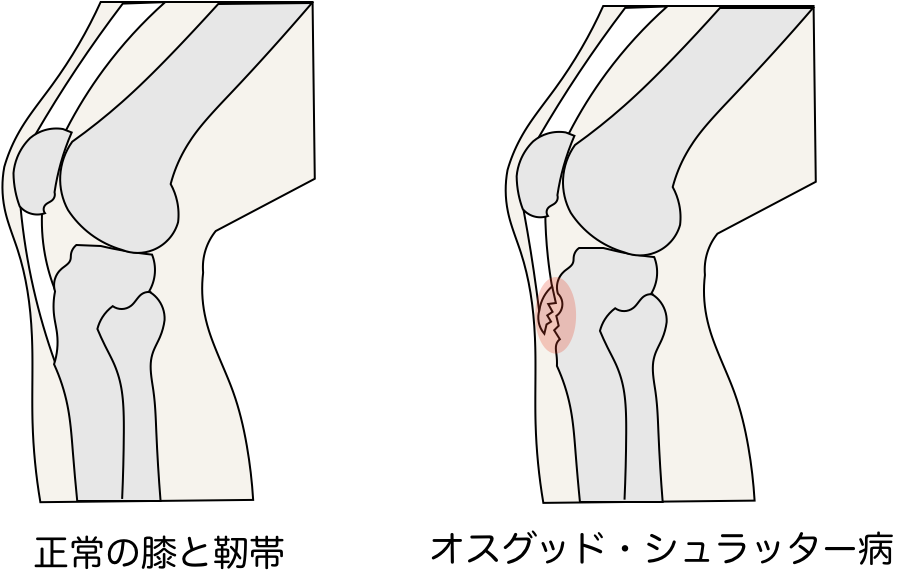

オスグッド・シュラッター病

主に10歳以降の成長期にジャンプやランニングなど膝を伸ばす筋の牽引によっておこる脛骨結節での成長軟骨の障害です。

成長期の子供の膝下(脛骨粗面)は大人と異なり軟骨部分が多く、弱いので運動など繰り返す刺激でダメージを受け、炎症がおきやすいです。

その結果、ひどい場合は軟骨の一部が剥離することがあり腫れていたり、歩くのが困難な場合は重症の可能性があります。

似た疾患にジャンパー膝などがあり、全て膝伸展機構の障害となります。